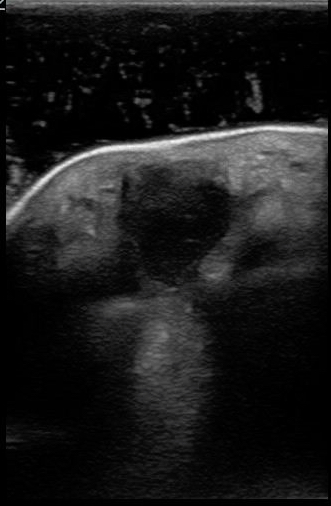

An abscess is a collection of pus or dead white blood cells in response to a SSTI. Antibiotics may be ineffective as a primary treatment and POCUS can help identify which patients require incision and drainage. In contrast to cellulitis, the typical appearance of an abscess on POCUS is an anechoic collection of fluid. There may be some internal echoes as dense pus or internal debris may coalesce. Occasionally, the debris or pus may be so profound that the abscess almost appears like soft tissue. When this occurs, adding downward pressure to the ultrasound transducer will make the pus move around. This is often called a “swirl sign” and helps identify the abscess. Importantly, POCUS allows the clinician to identify the coexistence of cellulitis and abscess or an isolated abscess and unnecessary antibiotics may be avoided. Figure 4 and 5 demonstrate the typical appearance of abscesses with POCUS.

FIGURES 4 AND 5. TYPICAL APPEARENCE OF ABSCESSES WITH POCUS. ANECHOIC OR HYPOECHOIC COLLECTION OF FLUID WITH INTERNAL ECHOES FROM PUS/DEBRIS.